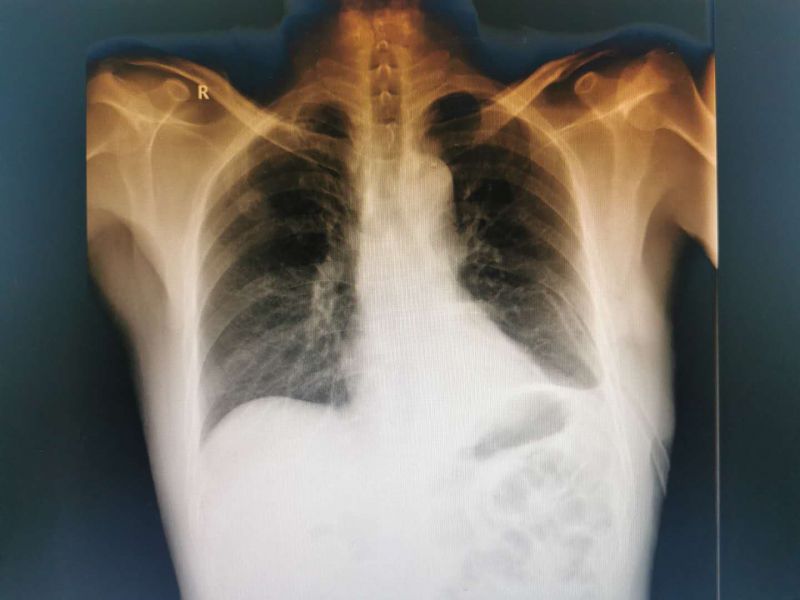

患者男性,51岁,因“反复胸闷”入我院心血管内科住院治疗,完善检查发下左下肺占位,经我科医师会诊后考虑“左下肺占位:恶性肿瘤可能性大”建议积极手术治疗。转入我科后予积极完善术前检查,经充分术前准备及术前讨论评估后在黄勇科主任为首的心胸外科团队努力下成功实施了单操作孔VATS下左下肺叶切除术并进行了系统淋巴结清扫,手术非常顺利,出血甚微。

患者CT影像学表现